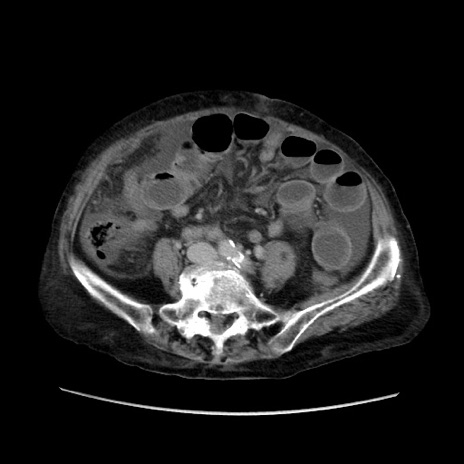

症例31(横断像)

【症例】80歳代 女性

【主訴】腹部膨満感

【現病歴】他院にて肝硬変にてフォロー中。1週間前から便秘、腹部膨満感、臍部腫瘤あり受診となる。

【既往歴】肝硬変

【身体所見】腹部膨隆あり、皮膚変化なし、疼痛なし。

【データ】WBC 4600、CRP 0.25